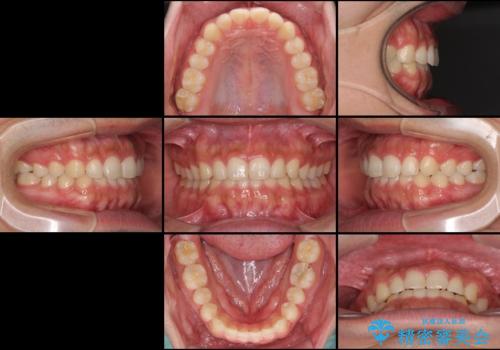

インビザラインによる、すきっ歯の改善

咬合力で上の前歯が前方に押し出されるようにして隙間ができていましたが、矯正治療により全て閉じることができました。

深い咬み合わせも多少改善され、隙間も閉じたことで、前方に出ていた前歯が引っ込んだため、口も閉じやすくなったとのことでした。